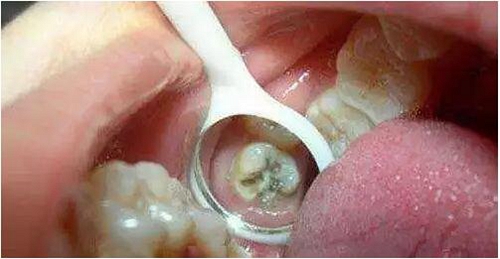

*牙髓炎:深齲由于齲洞離牙髓比較近,齲洞內(nèi)的細(xì)菌和細(xì)菌所產(chǎn)生的毒素容易滲透到牙髓組織,引起牙髓炎,使患牙發(fā)生劇烈疼痛。這個(gè)階段,根管治療是唯一可行的辦法。治療時(shí)需要麻醉后將牙髓組織清除,即大家所說(shuō)的“殺神經(jīng)”。

*根尖炎:牙髓炎得不到及時(shí)治療,或治療不徹底,細(xì)菌可通過(guò)牙髓向根尖擴(kuò)散,引起牙齒根尖部的病變,如根尖炎、根尖周炎、根尖膿腫等不同疾病。根尖部的病變急性發(fā)作時(shí)也會(huì)引起較重的疼痛,甚至牙齦及面部腫脹。根尖炎也需要行根管治療。